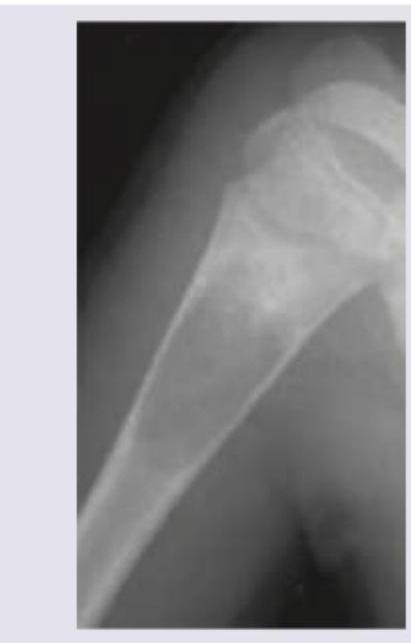

A 15-year-old boy presents with pain in the right upper arm and stiffness after playing cricket in the school. Since the complaints of the child were persisting, the family physician performed X-ray of right upper arm. The X-ray humerus shows presence of:

Explanation: ***Unicameral bone cyst*** - The X-ray image shows a **lucent lesion** in the metaphysis of the humerus, consistent with a **unicameral bone cyst (UBC)**. These cysts are common in children and adolescents, typically located in the proximal humerus or femur, and can present with pain after minor trauma due to **pathological fracture**. - The age of the patient (15-year-old boy), location (right upper arm/humerus), and presentation (pain after playing cricket indicating a potential pathological fracture) all align with the characteristics of a UBC. *Aneurysmal bone cyst* - While aneurysmal bone cysts (ABCs) can occur in similar age groups and locations, they typically present as **multiloculated, expansile, eccentric lesions** with thin bony septa, often described as a "blown-out" appearance. - The image provided shows a more uniform lytic lesion without prominent septations or extensive cortical expansion, making ABC less likely. *Osteoblastoma* - **Osteoblastoma** is a benign bone tumor that often presents with localized pain, but it is typically a **sclerotic or mixed lytic-sclerotic lesion**, sometimes with a nidus, and not a purely lucent, cystic lesion like the one seen. - It most commonly affects the spine and long bones, but its radiographic appearance would differ significantly from the image. *Osteoclastoma* - **Osteoclastoma**, also known as **giant cell tumor of bone**, typically occurs in individuals in their 20s to 40s, often at the **epiphysis** of long bones (e.g., distal femur, proximal tibia, distal radius) after epiphyseal plate closure. - While it is a lytic lesion, its characteristic location and patient age range make it a less likely diagnosis for a 15-year-old with a metaphyseal lesion in the humerus.